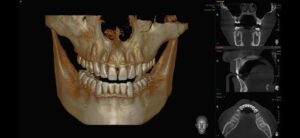

МРТ зубов: преимущества обследования

Магнитный резонанс представляет собой тестовый метод, используемый для диагностики заболеваний зубов, твердых и мягких челюстей и хряща. Магнитный резонанс считается небольшим эффективным методом исследований из-за большого количества артефактов из зубов. Анатомия челюсти Челюсть соответствует функциям кусания и жевательной еды и произношения. В верхней челюсти есть носа носа, а нижняя челюсть — единственная движущаяся часть черепа. …